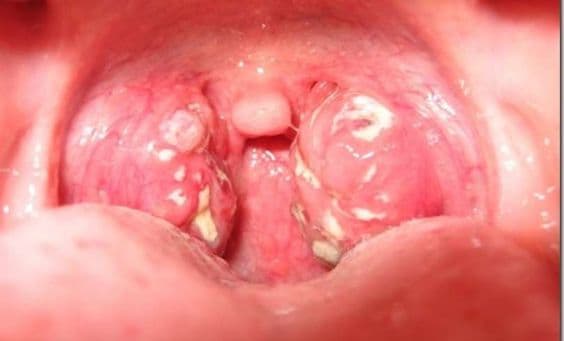

Viêm họng hạt mãn tính là một dạng quá phát của bệnh viêm họng mãn tính. Bài viết dưới đây sẽ cung cấp cho quý vị phương pháp điều trị bệnh phù hợp. 1. Thế nào là viêm họng hạt mãn tính? Viêm họng hạt thường hình thành phía sau thành họng, các hạt có […]